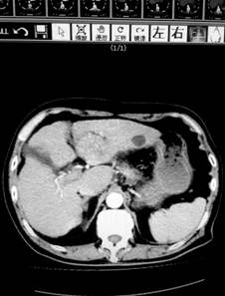

上午9點(diǎn),第一肝門預(yù)阻斷后,肝臟手術(shù)正式開始,患者是一位80歲的肝癌患者,腫瘤位于肝左葉,合并肝炎并肝硬化,考慮患者肝功能較差,依據(jù)腫瘤根治原則,為患者成功實(shí)施了左肝外葉切除。目前該患者正在進(jìn)一步康復(fù)。